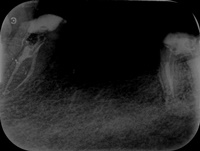

Reendo dolnej szóstki.

Wykonany zabieg resekcji wierzcchołka nie pomógł w ustąpieniu obajawów zapalnych. Skuteczne okazało sie dopiero reendo.